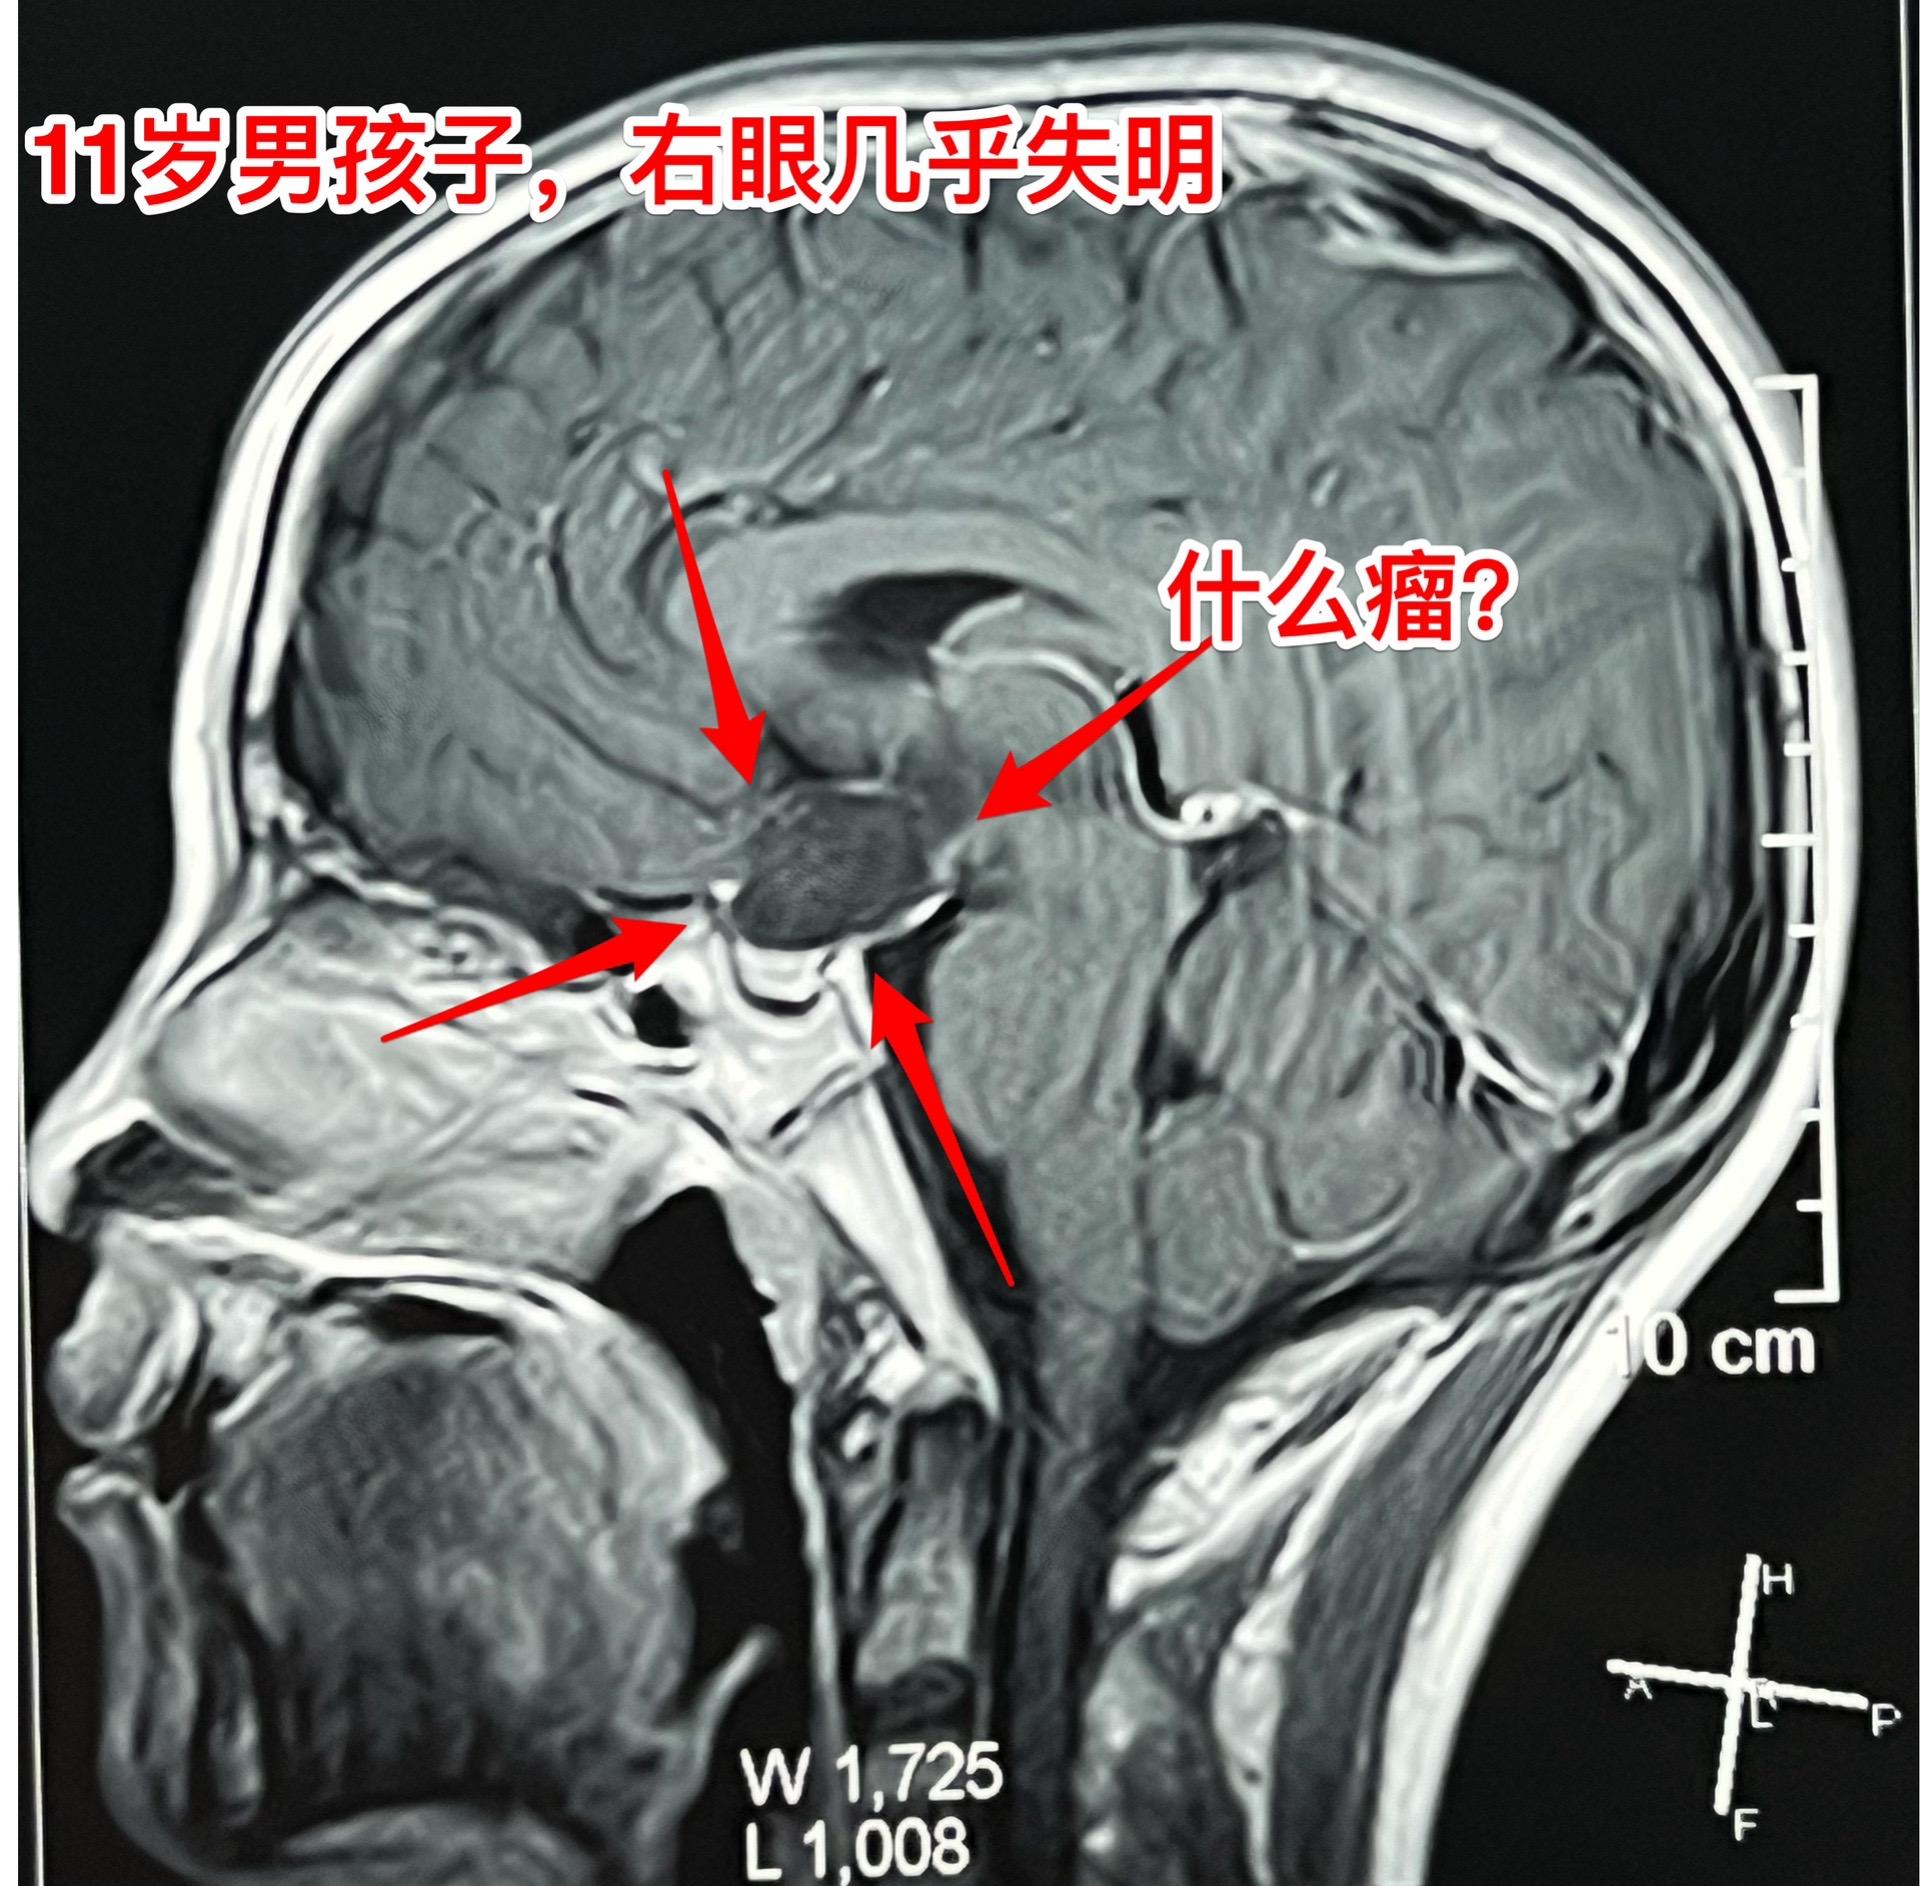

鞍区皮样囊肿比颅咽管瘤更罕见。11岁的湖北男孩子在学校体检查视力发现右眼几乎失明了,看不见东西,只有光感! 而他自己却不知道!平时也没有感到头痛,没有太多的不适。这个孩子是多粗心呀! 随后行脑部CT和磁共振检查发现鞍区 有个肿瘤,怀疑为颅咽管瘤。CT显示肿瘤没有钙化,这一点不符合颅咽管瘤。 5月31日作了开颅手术,将病灶完全切除。病灶的囊皮是灰色的,内部有油脂样的粘滞物,还含有毛发。所以术中诊断为皮样囊肿。这是近10年以来的第三例鞍区皮样囊肿手术。前两例